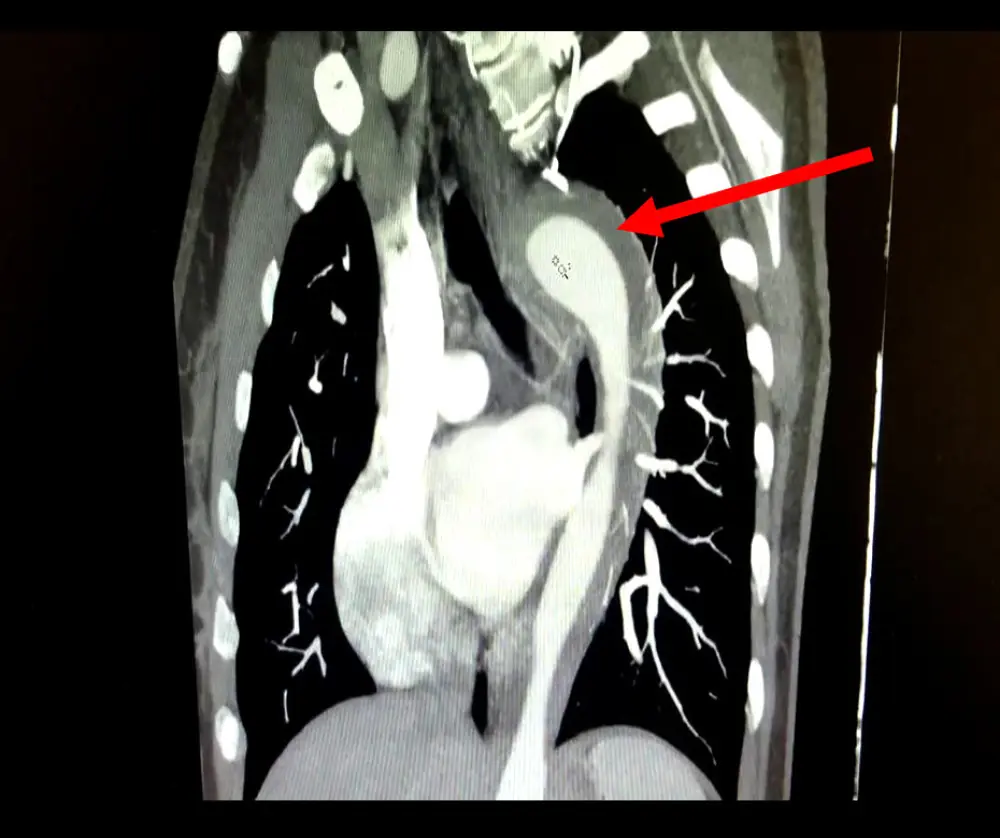

When the woman was examined at the hospital, medical staff discovered that she experienced a form of acute aortic syndrome (AAS) - a potentially life-threatening condition.

Doctors found a leak in her aorta - a large artery that carries blood through the body. The condition is very scary, as for every hour a patient has not been treated, their odds of death rise by one percent.